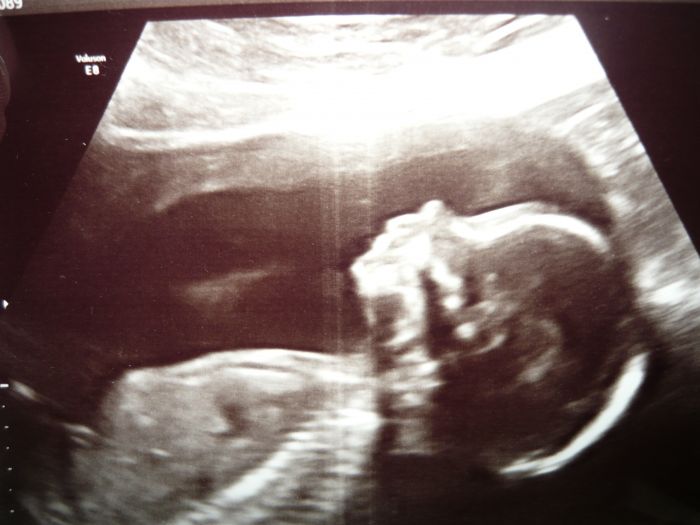

My jsme byli na genetice ve 20. týdnu a malej se nechtěl otočit a paní Dr. neviděla na srdíčko tak mě poslala se procházet, aby se otočil a dát si kapučíno z automatu. Kdyby se neotočil, musely bychom do Olomouce znovu. Procházka zabrala, vše je v pořádku a bude to kluk. Manželovi se líbí Radim a mě Lukášek. Už má 22 cm

Přidám fotečku

Karol super, že jste v pořádku, fotečka úžasná, je super když můžeme ty naše prcky vidět už v bříšku viď?

Karol, super, že vše dobře dopadlo. Teď už jen vybrat to jméno ;-) Ta fotečka je úplně suprová